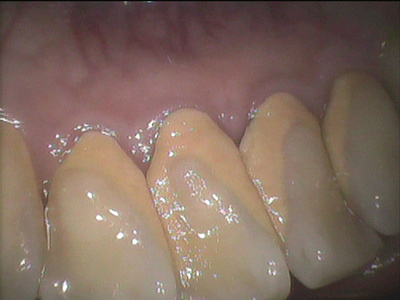

歯の裏を見てみるとこのようにビッシリかたい石のようになったものがこびりついています。これが歯石です。歯の石と書くくらいなのでとても硬いです。この状態になると歯ブラシでご自身で取り除くことはできません。歯科医院で専用の機械、超音波スケーラーという器具で除去しないと取れません。